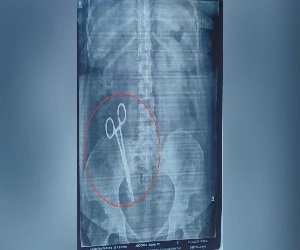

लखनऊ: यूपी की राजधानी लखनऊ से एक हैरान कर देने वाला मामला सामने आया है। यहां एक महिला के पेट में डॉक्टरों ने 17 साल पहले कैंची छोड़ दी थी। मामले का खुलासा तब हुआ जब महिला का एक्स-रे कराया गया। वहीं एक्स-रे की रिपोर्ट मिलने के बाद महिला के पेट में कैंची होने की बात सामने आई, जिसके बाद परिजनों के होश उड़ गए। बताया जा रहा है कि महिला का 17 साल पहले ऑपरेशन हुआ था, जिसके बाद से ही कैंची पेट में थी। वहीं घटना सामने आने के बाद महिला के पति ने गाजीपुर थाने में लापरवाही बरतने वाली डॉक्टर के खिलाफ शिकायत दर्ज कराई है।

दरअसल, लखनऊ में एक महिला का एक्स-रे कराने के बाद उसके पेट में कैंची होने की बात सामने आई। इस घटना के बाद महिला के पति ने गाजीपुर थाने में शिकायत दर्ज कराई है। वहीं KGMU में ऑपरेशन के बाद महिला के पेट से कैंची को निकाला गया है। महिला के पति अरविंद पांडे ने शिकायत में बताया है कि उन्होंने 26 फरवरी 2008 को अपनी पत्नी को इंदिरानगर के ‘शी मेडिकल केयर’ में भर्ती कराया था। यहां डॉक्टर पुष्पा जायसवाल के द्वारा ऑपरेशन किया गया, जिससे उन्हें बच्चा पैदा हुआ। ऑपरेशन के कुछ समय बाद तक सब ठीक रहा, लेकिन कुछ दिनों के बाद महिला को विभिन्न प्रकार की समस्या होने लगी।

पीड़ित ने शिकायत में आगे कहा है कि वह काफी लंबे समय से अपनी पत्नी का इलाज करा रहा था। इस बीच 23 मार्च 2025 को जब उसने अपनी पत्नी का एक्स-रे कराया तो पेट में कैंची होने की बात पता चली। इसके बाद उन्होंने अपनी पत्नी को केजीएमयू में दिखाया। यहां 25 मार्च 2025 को मेडिकल परीक्षण के बाद उनकी पत्नी को भर्ती कर लिया गया और 26 मार्च 2025 को ऑपरेशन के पश्चात पेट से कैंची निकाली गई। पीड़ित ने लापरवाह डॉक्टर पुष्पा जायसवाल के खिलाफ कार्रवाई की मांग की है।